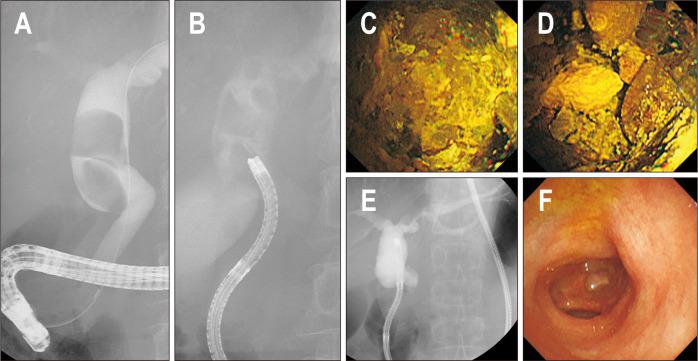

BACKGROUND/AIMS: Treatment options for difficult bile duct stones are limited. Direct peroral cholangioscopy (POC)-guided lithotripsy may be an option. A newly developed multibending (MB) ultraslim endoscope has several structural features optimized for direct POC. We evaluated the utility of direct POC using an MB ultraslim endoscope for lithotripsy in patients with difficult bile duct stones.

Twenty patients with difficult bile duct stones, in whom stone removal using conventional endoscopic methods, including mechanical lithotripsy, had failed were enrolled from March 2018 to August 2019. Direct POC-guided lithotripsy was performed by electrohydraulic lithotripsy or laser lithotripsy. The primary outcome was complete ductal clearance, defined as the retrieval of all bile duct stones after lithotripsy confirmed by balloon-occluded cholangiography and/or direct POC.

The technical success rate of direct POC was 100% (20/20), and the free-hand insertion rate was 95% (19/20). Direct POC-guided lithotripsy, attempted by electrohydraulic lithotripsy in nine patients (45%) and laser lithotripsy in 11 patients (55%), was successful in 95% (19/20) of the patients. Complete ductal clearance after direct POC-guided lithotripsy was achieved in 95% (19/20) of patients. Patients required a median of 2 (range, 1-3) endoscopic retrograde cholangiopancreatography sessions for complete stone removal. Adverse event was observed in one patient (5%) with hemobilia and was treated conservatively.

Direct POC using an MB ultraslim endoscope was safe and effective for lithotripsy in patients with difficult bile duct stones.